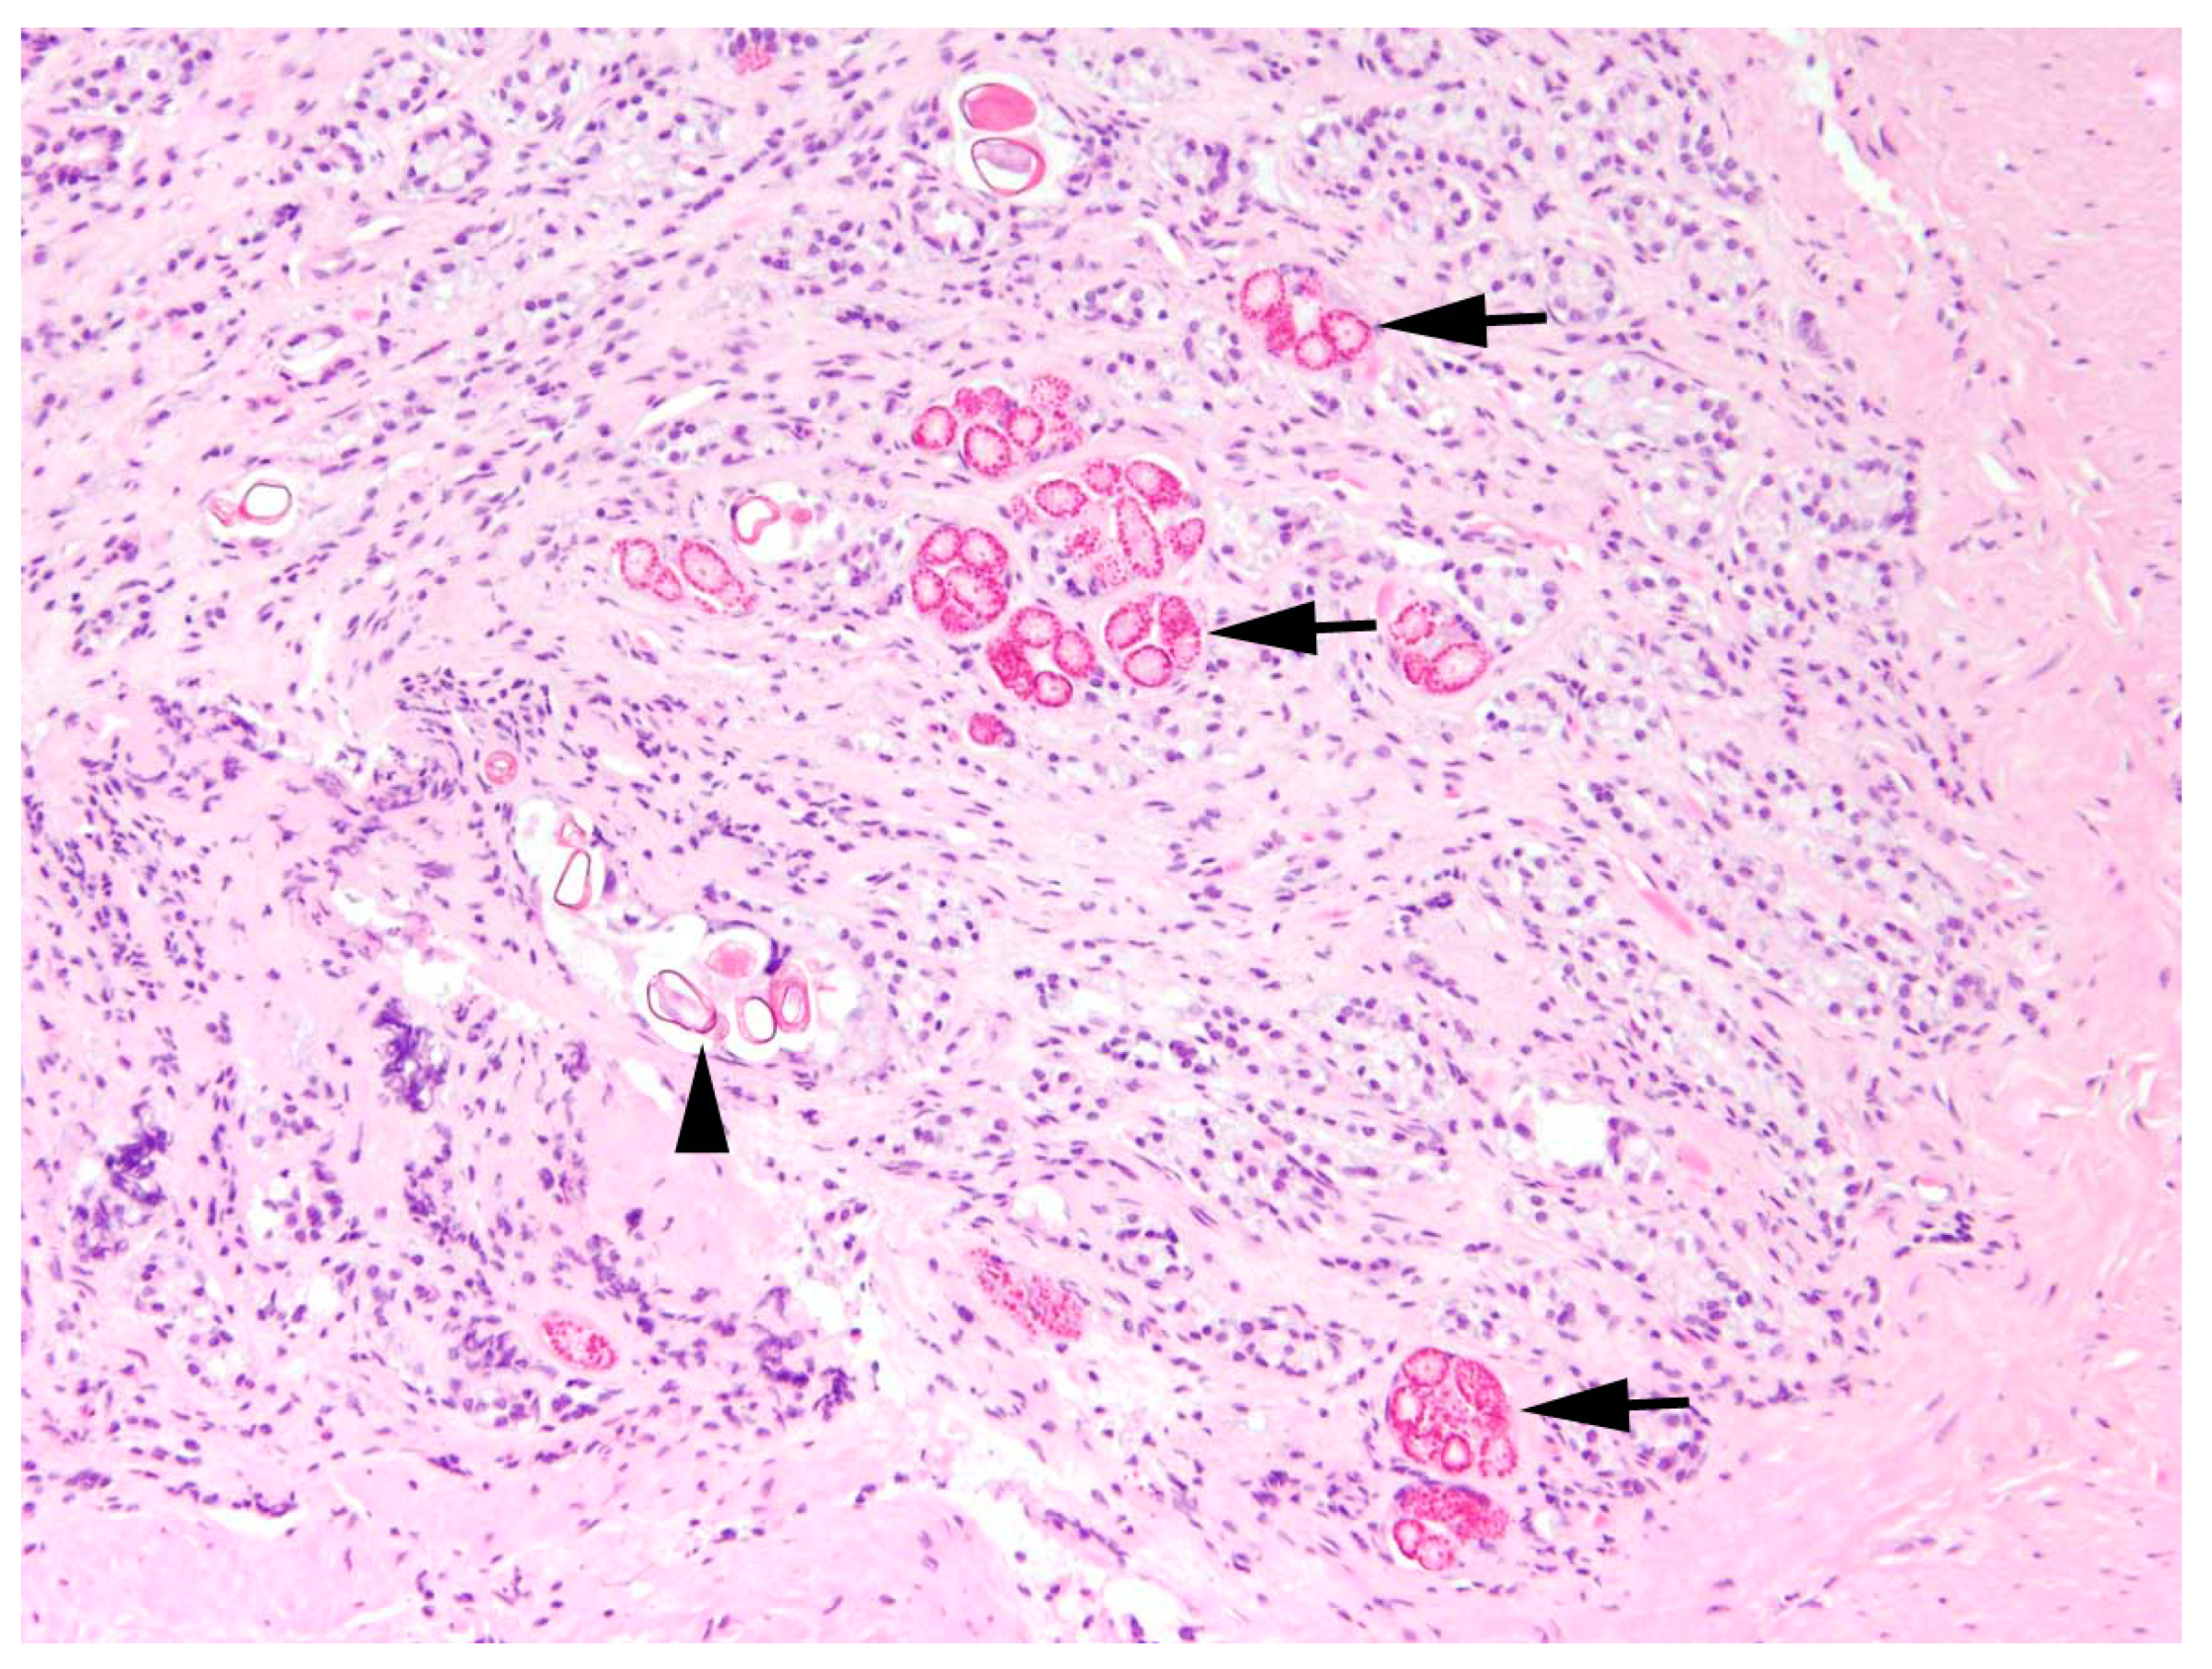

The main type of hepatitis was non-purulent with different proportions of lymphocytes, plasma cells, and macrophages (93.0%, n = 80;

Figure 4), followed by purulent (14.0%, n = 12), necrotising (5.8%, n = 5), and granulomatous type (5.8%, n = 5). Eight cases (9.3%) of hepatitis showed a mixed inflammatory type.

Occasionally, hepatic fibrosis (15.1%, n = 13) or liver cell necrosis (15.1%, n = 13) were associated with hepatitis (